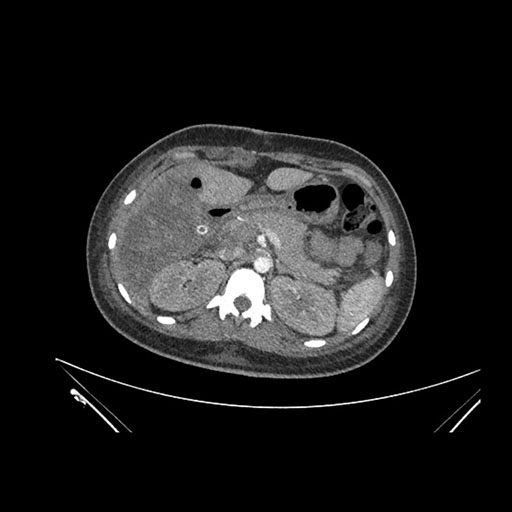

Imaging Analysis

Look through the patient's CT scan to identify any areas of concern for the necessary procedure.

Coronal Arterial

Based on initial findings, which issue(s) would you be most concerned about?